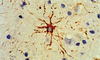

What is a gemistocyte?

***KNOW THIS***

Swollen astrocytes- cytoplasm contains pink “glassy” material